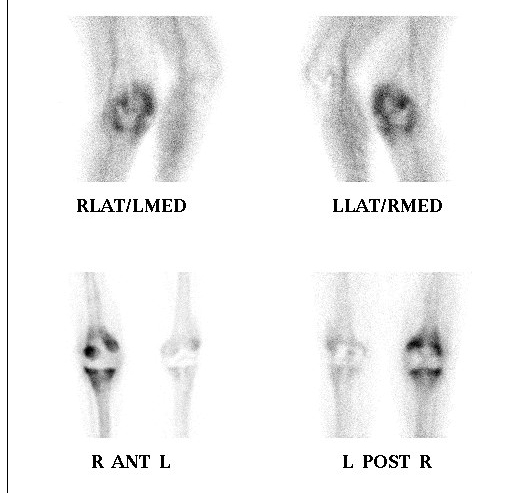

Peters et al J Arthroplasty 2009

Avoid by

- careful reaming and drilling osteoporotic bone

Management

1. Rotate metaglene

- use locking screws to stabilise glenoid

2. PA screws

- cannulated 4.0 mm screws

- inserted percutaneously from posterior

Great deal of dead space is created

- always use a drain